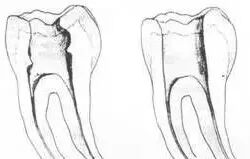

1. 便宜形态

便宜形态是自切端或咬颌面朝向根尖的直线开扩尖锥形态,减少污染物推出根尖孔,方便冲洗、根管充填和侧壁施压。

2. 保持形态

保持形态是根尖狭窄部内 1 — 2mm 的一段距离,由扩大器回转切割而不贴根管壁提拉切割制成,是扩大器的原始形态(近似平行)。在测试主牙胶尖时给测试者有一个牵引抵抗 (tugback) 的感觉。

3. 抵抗形态

抵抗形态是根管预备的根尖形态,它是由扩大器或根管锉尖端 75 度角自然切割而成。其目的是防止根管充填材超出根尖孔,并且使根尖封闭更加严密。